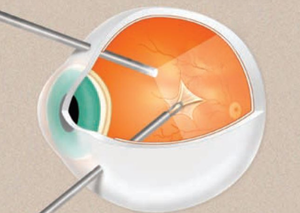

Закрита вітректомія

Закрита вітректомія — це мікрохірургічна процедура, яка використовується для лікування захворювань та пошкоджень сітківки і скловидного тіла ока. Вона відноситься до видів операцій на задньому відділі ока.

Як проводиться вітреоретинальна хірургія?

Вітреоретинальна хірургія зазвичай проводиться під місцевою анестезією. Процедура включає кілька основних етапів:

- Підготовка ока – введення анестезуючих крапель для знеболення.

- Створення мікроскопічних розрізів– для введення інструментів у порожнину ока.

- Видалення патологічних тканин – за допомогою спеціальних інструментів.

- Введення газу або силіконової олії – для підтримки сітківки на місці.

- Закриття розрізів – після завершення операції.